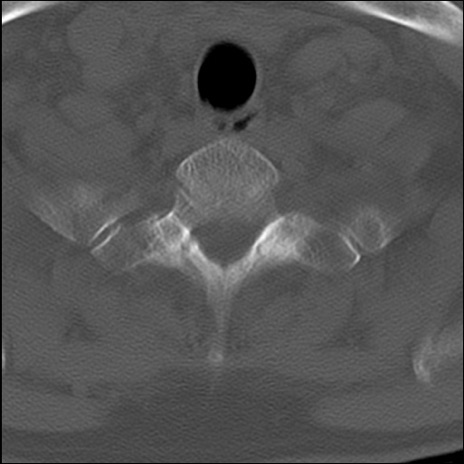

症例48 頚椎CT(横断像)

頚椎CT